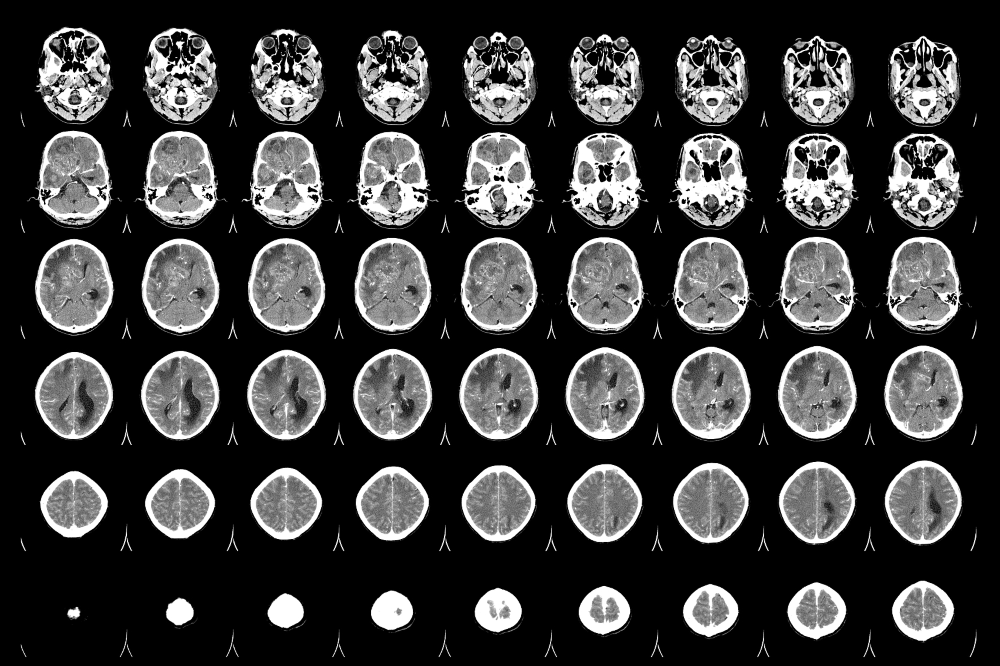

【昆明医科肿瘤医院】胶质瘤的临床表现

胶质瘤是一种常见的原发性脑肿瘤,其临床表现与肿瘤的大小、位置和病理类型有关。本文将介绍胶质瘤的临床表现。头痛头痛是胶质瘤最常见的症状之一,约有50%的患者会出现头痛。头痛通常是间歇性的,而且常常在早上或半夜醒来时出现。头痛的程度和位置也有所不同,有些患者可能感...